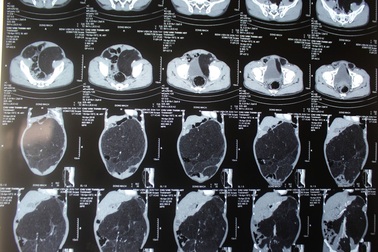

Đau bụng dữ dội do tắc động mạchNhập viện với triệu chứng đau bụng dữ dội, sốt, bệnh nhân được chuẩn đoán bị tắc động mạch mạc treo tràng trên do bóc tách và huyết khối.

Đi khám đau bụng, phát hiện u khủng lớn hơn 10kgBệnh nhân luôn thấy đau bụng, ăn vào là khó chịu, khó tiêu. Tình trạng này kéo dài suốt 6 tháng bệnh nhân mới đến viện khám, ngỡ ngàng khi bác sĩ chuẩn đoán khối u mạc treo trong ổ bụng kích thước 40cm, nặng hơn 10kg.